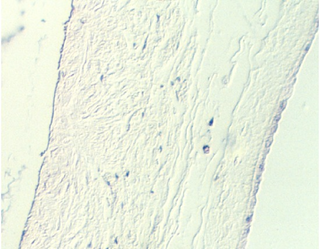

Both the maternal and fetal components are seen in the larger section on slide 89. As a landmark, look for the amniotic side of the chorionic plate. This actually shows the amniotic sac. Then, move into the chorionic plate and identify the stem villi originating from this plate. The following figure shows the amnionic side.

The following photos show the portion facing the embryo. It is distinguished by the simple squamous epithelium. In the lower right corner, one can see the denser epithelium of the side facing the uterus.